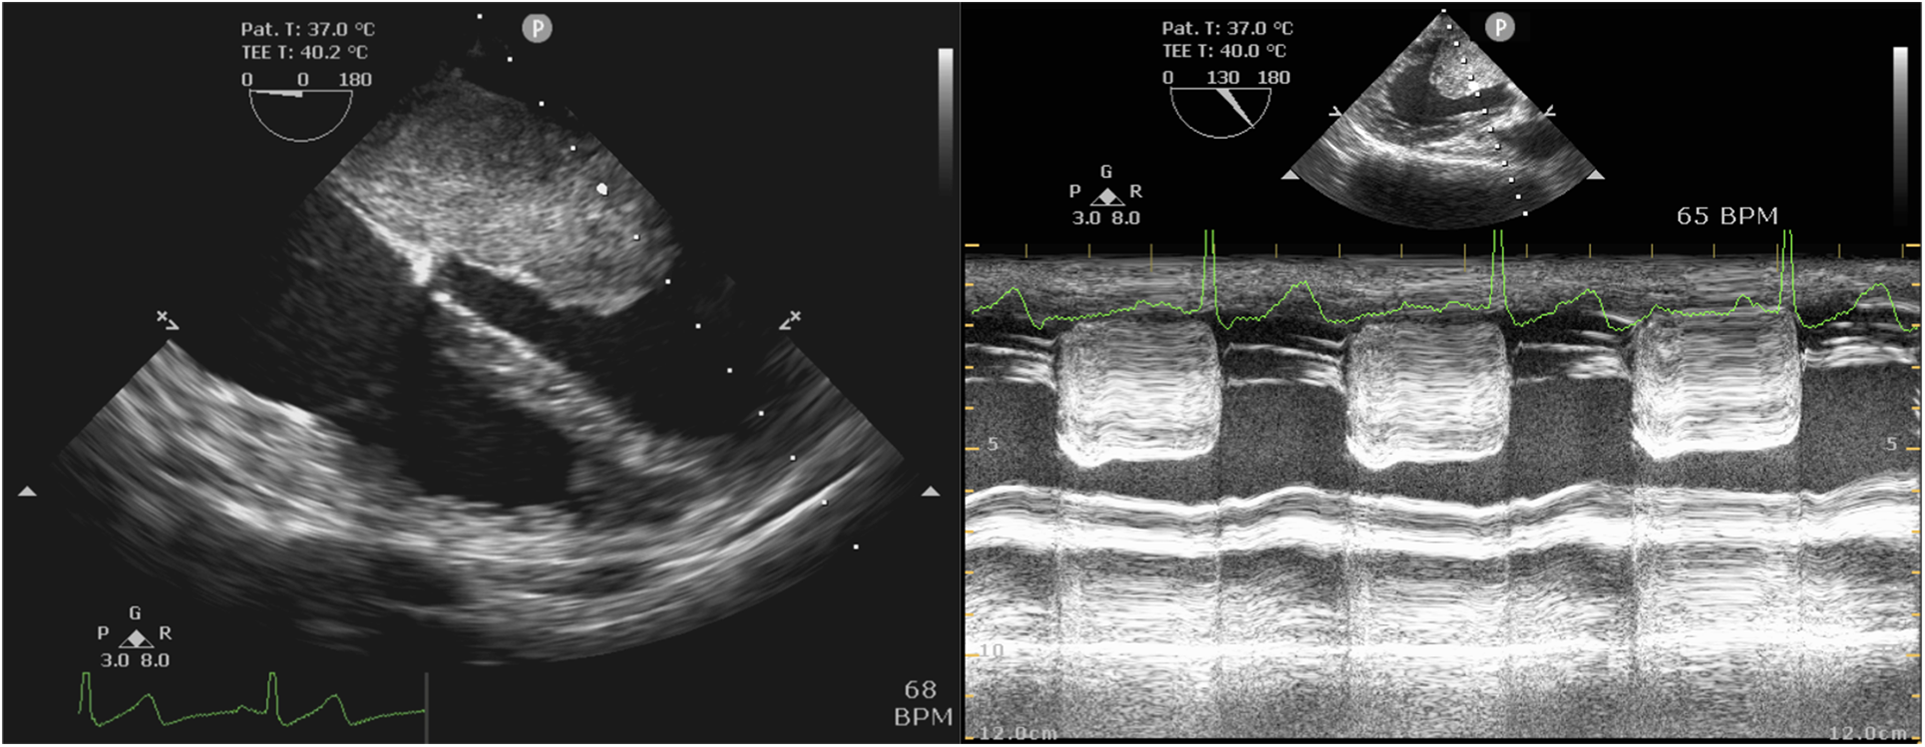

TEE revealed a mass attached to the interatrial septum in the left atrium, which obstructed the mitral orifice during diastole (Figure 3). As shown in Table 5, the mean postoperative mechanical ventilation duration was 12.52 ± 4.69 h, the mean LOS in the ICU was 41.97 ± 27.21 h, and the hospital 10.64 ± 3.01 days. In-hospital mortality did not occur in any of the cases analyzed. However, several postsurgical complications were reported. These included: atrial fibrillation (n = 1), incision infection (n = 1), pericardial effusion (n = 1), and postoperative bleeding which had reoperation experience (n = 1). Moreover, three patients underwent hospital readmission within 90 days after discharge. The reasons for hospital readmission varied from atrial flutter and persistent fever to pericardial effusion.

Figure 3

Intraoperative TEE examination. Left: Mid-esophageal four-chamber view showed the left atrial myxoma. Right: Mid-esophageal long-axis view by M mode demonstrated mitral obstruction.

TTE is a reliable method in diagnosing atrial myxomas, but not in all cases, such as emphysema, obesity, or chest deformity patients. At the same time, TEE has been found to always be reliable and valuable in assessing atrial myxoma (18, 30). Therefore, given the importance and utility of TEE perioperatively in patients undergoing myxoma resection, pre-CPB TEE was routinely performed, which helped confirm the diagnosis and monitoring and guide surgical resection. Post-CPB TEE would provide an assessment of valve and cardiac function following resection. Like many other studies (1, 7, 31, 32), we consider intraoperative TEE to be an indispensable instrument in the anesthesia management of cardiac myxoma resection.